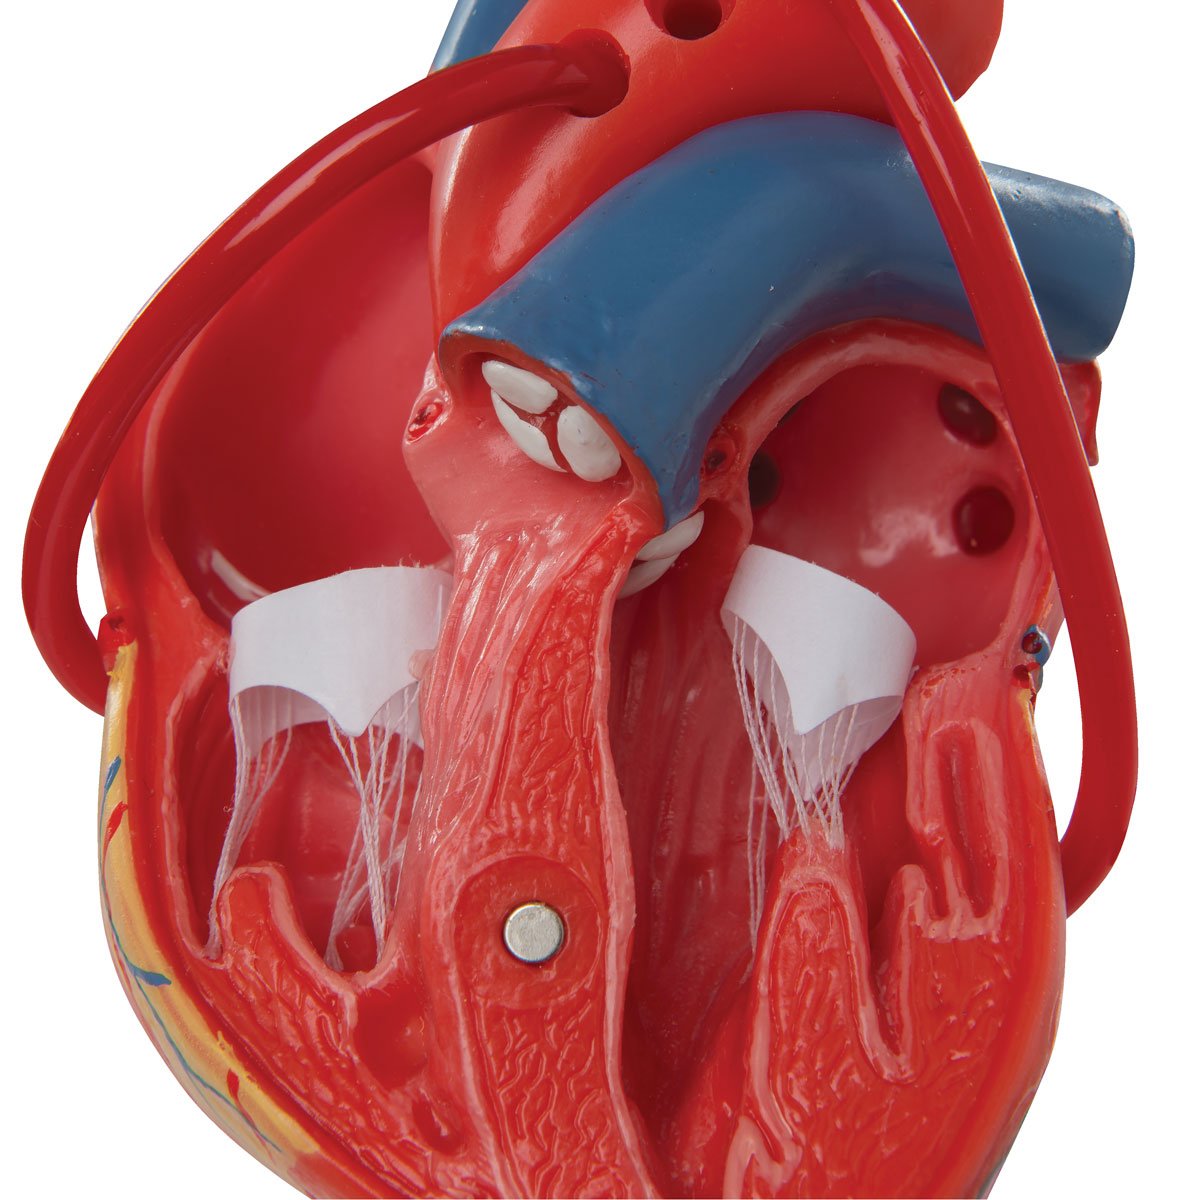

Anatomical models

Selling anatomical models is the mainstay of eAnatomi, although we also spend a lot of resources developing our own anatomical materials such as posters. Anatomical models are used for various purposes and can show both defined tissues, organs and organ systems. Are you looking for a simple model of bone tissue or perhaps an advanced torso model based on MRI technology, you can find it all at eanatomi.com.